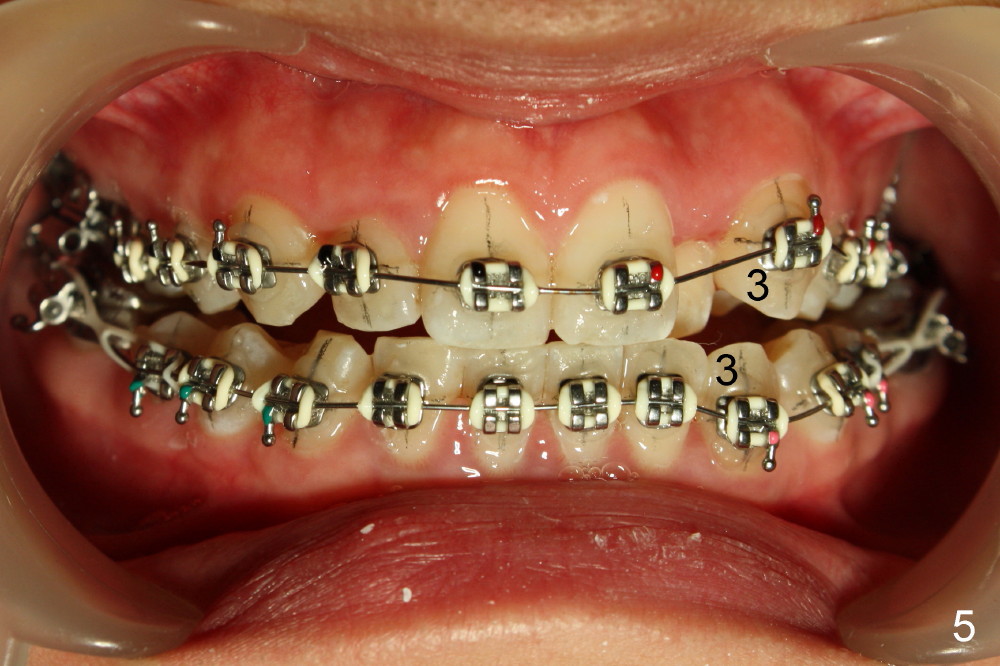

The rotation of LL5 is so severe that the bracket is forced to be placed distal to the height of contour due to interference of LL4 (Fig.4). Because of delayed eruption of L3s (Fig.5: 3), the first niti wires (.014") are bent the most around them. Power chain x2 are placed between L5 and 6 (Fig.6) to correct the rotation of the former in timely manner.

In one month, wires (.016 niti just installed) are straighter although there is slight open bite on the left (Fig.7, compare to Fig.5). It may be beneficial to ask the patient to use (next appointment) an elastic between L3,4s to reduce the open bite. Power chains are continuously used bilaterally between L5,6 (Fig.7,8).

Next visit wires are changed to .018 stainless steel (SS). The upper one should be expanded laterally (stretched outside) and lower inside before insertion to facilitate correction of posterior cross bite. An open coil spring will be placed between UL 1 and 3 to increase the space for UL2.